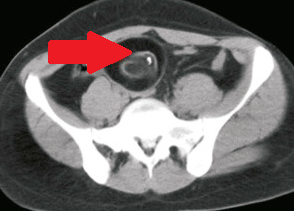

CT κοιλίας. Κόκκινο βέλος — Τυφλίτιδα. Σημαντική πάχυνση τοιχώματος τυφλού (Ευγενική παραχώρηση Dr. V. Penopoulos)